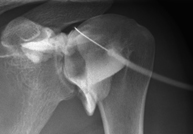

- X-ray arthrography

This X-ray based procedure involves injecting a contrast agent into the joint to detect lesions in certain structures (cartilage, bone, tendons, etc.) by observing the distribution of the contrast agent.

- Pelvis X-ray

This procedure uses X-ray imaging to examine the pelvis, especially the pelvic bones.

- Hip X-ray